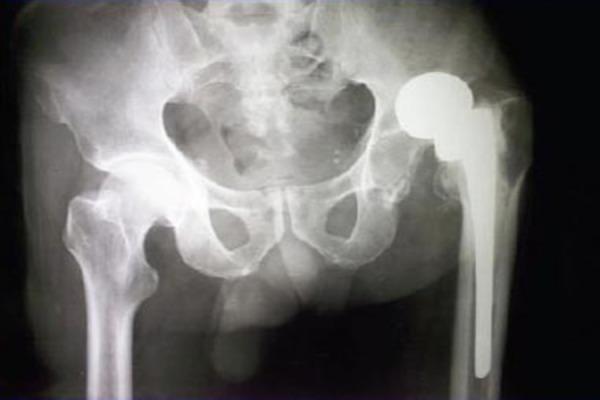

A 60 year farmer presented with fracture shaft femur and ipsilateral dislocation prosthesis of right hip. He had a hemiarthroplasty done for fracture neck of femur in the past but used to walk with a lurch since he started to ambulate after discharge. However he was satisfied despite "some problems" which had caused shortening of his limb. The patient was informed of the various treatment options and their possible complications. He expressed his inability to afford a Total Hip Arthroplasty (THA) at any stage and consented for other options discussed with him. The patient was positioned supine and adductor tenotomy done. Next he was positioned laterally and the fracture was fixed with heavy duty broad dynamic compression plate and screws. The wound was temporarily closed. Now through the previous scar via posterior approach the hip was exposed. The prosthesis was found to be firmly fixed to the proximal femur. The acetabulum was cleared with fibrous tissue. All attempts the prosthesis to relocate the prosthesis failed after several attempts and it was best decided to leave alone. Post operatively period was uneventful. At follow up he refused for any further manoeuvre in future inform of heavy traction and attempts to reduce the same. At one year when he was walking unaided and his X-rays showed that fracture had well united his SF-36 score was PCS - 49.6 and MCS - 51.9.

一名60岁的农民因股骨干骨折及同侧右髋关节假体脱位前来就诊。他曾因股骨颈骨折接受过半髋关节置换术,但自出院后开始行走以来一直跛行。尽管存在导致肢体缩短的“一些问题”,但他对此仍感到满意。我们向患者告知了各种治疗方案及其可能的并发症。他表示在任何阶段都无力承担全髋关节置换术(THA),并同意了与他讨论的其他方案。患者仰卧位,行内收肌切断术。接着将患者置于侧卧位,用重型宽动力加压钢板和螺钉固定骨折。伤口暂时缝合。现在通过先前的瘢痕经后路暴露髋关节。发现假体牢固地固定在股骨近端。用纤维组织清理髋臼。经过多次尝试,所有使假体复位的努力均告失败,最终决定不再尝试。术后恢复顺利。随访时,他拒绝在未来进行任何进一步的操作,如强力牵引及尝试复位。一年后,他已能独立行走,X线显示骨折已良好愈合,其SF - 36评分为:身体功能(PCS) - 49.6,精神健康(MCS) - 51.9。